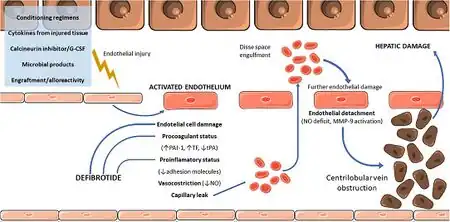

In the bone marrow transplant setting, hepatic veno-occlusive disease is felt to be due to injury to the hepatic venous endothelium from the conditioning regimen. Toxic agents causing veno-occlusive disease include plants as well as the medication cyclophosphamide.

Treatment generally includes supportive care including pain management and possibly diuretics.[7] In those with severe disease due to a bone marrow transplant, defibrotide is a proposed treatment.[8] It has been approved for use in severe cases in Europe and the United States.[9][10] A placebo controlled trial, however, has not been done as of 2016.[7]